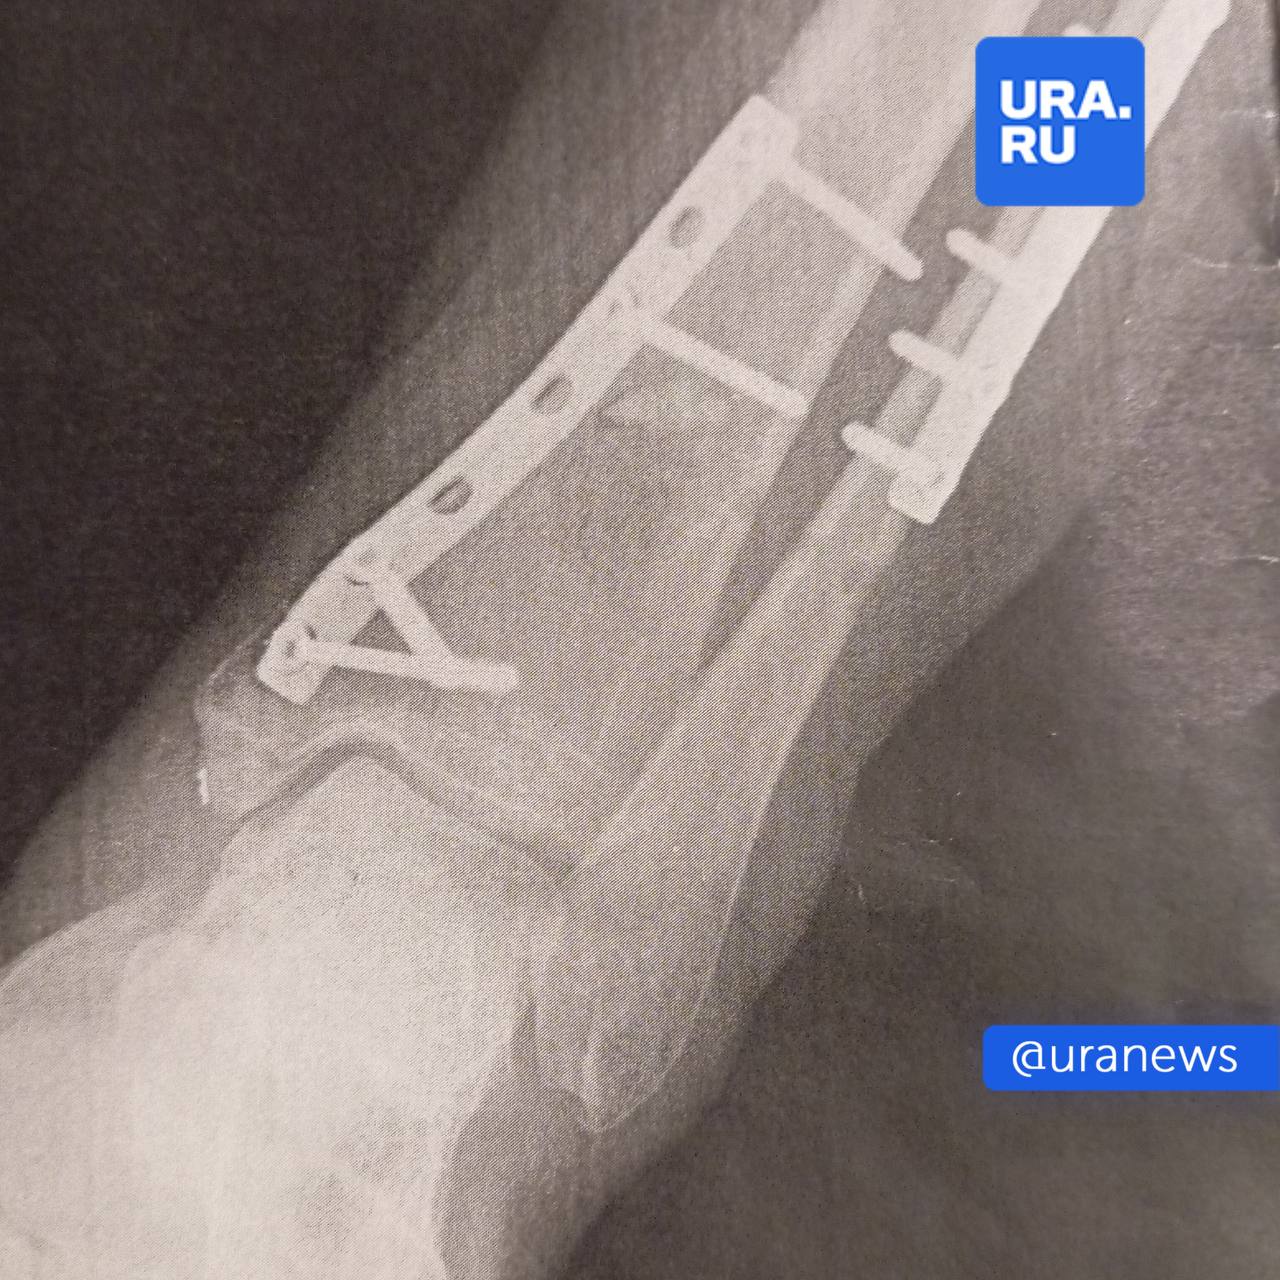

Жительнице Перми раздробило кости в фитнес-клубе — она не могла ходить два месяца и перенесла три операции.

Во время тренировки на ногу женщины рухнул 50-килограммовый груз. Она подала в суд.